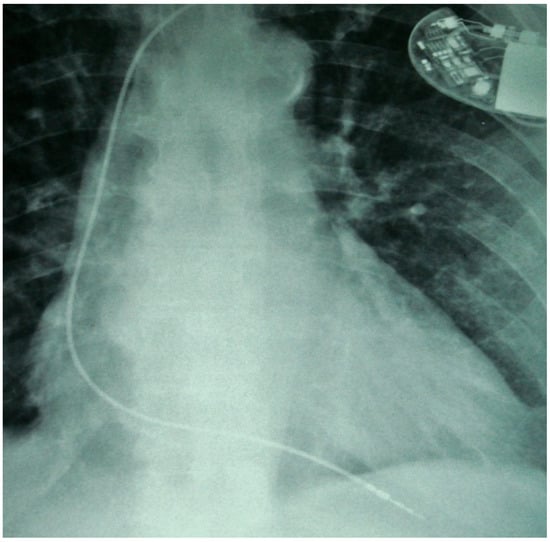

Twiddler’s Syndrome: Predictors, Prevention, and Outcomes in a Case Series

Background/Objectives: Twiddler’s syndrome is an uncommon but clinically important complication of implantable cardiac devices, in which generator rotation within the pocket results in lead torsion, lead retraction, and device malfunction. Recurrence can necessitate repeated surgical intervention and may be preventable through early risk identification and procedural strategies. Methods: We describe a single-centre case series of three female patients with pacemaker-associated Twiddler’s syndrome. Clinical presentation, timing of lead retraction, management strategies (including pocket location and fixation approach), recurrence, and follow-up outcomes were reviewed. Results: All patients were older women and developed symptomatic device failure early after implantation, with radiographic confirmation of lead retraction and coiling occurring within three weeks in all cases. Recurrence was observed when enhanced preventive measures were not employed. Notably, in one patient, recurrence occurred after an initial revision in a second prepectoral pocket, prompting subsequent reimplantation in a subpectoral location with reinforced fixation and structured patient and family counselling, after which no further recurrence occurred at one year. In the remaining cases, revision with reinforced generator fixation and counselling was associated with stable lead position and satisfactory device function during follow-up. Conclusions: Twiddler’s syndrome most commonly presents in the first weeks following implantation. Proactive identification of at-risk patients and consideration of reinforced fixation and pocket strategies at the index procedure may reduce recurrence and avoid repeat interventions.

Figure 1